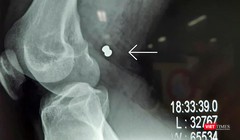

Phim X-ray chụp viên đạn ghim vào đùi gây vở động mạch và tĩnh mạch đùi của bạn nhân

Thoát chết sau khi bị súng hơi bắn đứt động mạch và tĩnh mạch đùi

VietTimes – Sau 5 tiếng đồng hồ phẫu thuật và truyển hết 1,5 lít máu, êkíp các bác sĩ Bệnh viện Vĩnh Đức (Quảng Nam) đã cứu sống bệnh nhân bị súng hơi bắn đứt động mạch và tĩnh mạch đùi.